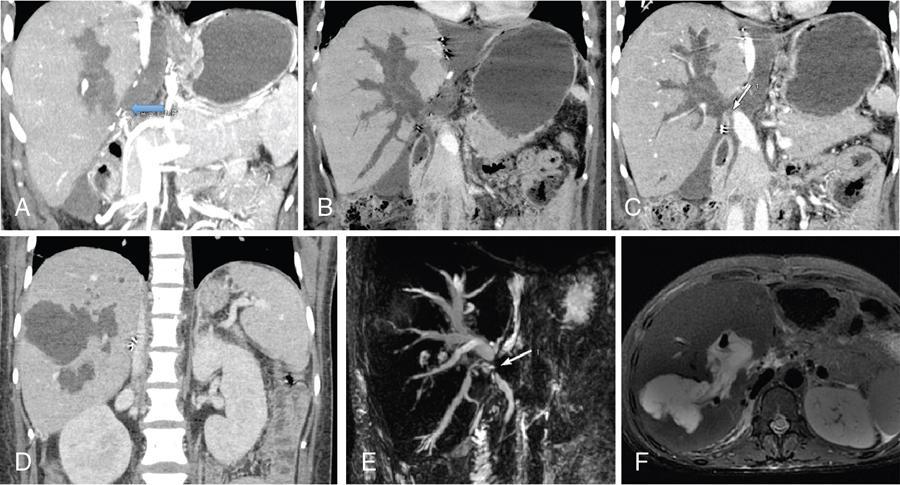

Imaging plays a significant role to make an early diagnosis and establish the best treatment options for posttransplant complications as clinical manifestations and laboratory parameters in many of the complications are usually nonspecific and overlapping. The imaging evaluation of postoperative complications remains the same in both types of liver transplants (DDLT and LDLT). Ultrasound with colour Doppler is usually the first modality of choice in the immediate postoperative period due to its easy and bed side availability with high accuracy and ability to pick up all major posttransplant complications, though it has a drawback of being operative dependent. It is usually part of regular postoperative assessment of the recipient for initial few postoperative days, playing an important role in picking up early complications. It is essential for the radiologist to know the details of the individual patient’s postoperative anatomy and surgical details, since anastomoses are the locations where complications occur most frequently. Goals of ultrasound evaluation in early postoperative period: Vascular evaluation with colour Doppler: CT/MRI imaging plays a supportive role for confirmation of the findings seen on ultrasound or colour Doppler or is done as an advanced imaging in case of mismatch between clinical or laboratory parameter and ultrasound or Doppler findings. MRI is particularly important for assessment of the biliary tree. First postoperative Doppler is done within 24 hours of the surgery and it serves as the baseline for comparison in the future. The haptic artery needs to be evaluated at the anastomotic site and also in the intrahepatic portions and the parameters to be evaluated are the systolic upstroke, PSV and resistive index (RI). Table 9.14.16 gives normal ranges of these parameters. Normal hepatic artery Doppler waveform demonstrates rapid systolic upstroke, with a systolic acceleration time (SAT) of less than 0.08 second and continuous diastolic flow, displayed above the baseline. A wide variability is observed in PSV of HA in the immediate postoperative period even in the absence of any hepatic arterial complication. Normal values may vary averagely from 40 to 120 cm/s. Vascular kinks or anastomotic site oedema in postoperative period can lead to falsely increased PSV in the HA. Correction of Doppler angle must be kept in mind while measuring the PSV of HA so that the angle aligns with the direction of the artery and must be less than 60 degrees to avoid inaccurate results. The hepatic arterial RI is an important tool to assess the hepatic arterial waveform in postliver transplant setting, as it allows semiquantitative estimation of the resistance to arterial flow into the liver. The normal RI ranges from 0.55 to 0.80 in posttransplant patients. The RI increases with decrease in the diastolic flow in the hepatic artery, which suggests increased resistance to the hepatic arterial flow. Absence or reversal of diastolic flow in the hepatic artery corresponds to an RI of 1.0 It is important to note that, increased RI of the hepatic artery (greater than 0.8) is a normal findings in the first few days after liver transplantation, due to decreased diastolic flow, which is attributed to allograft oedema, increased cold ischemia time, increased portal flow or vessel spasm. These transient arterial waveform abnormalities in early postoperative period usually resolve and normalize in 7–15 days on the follow-up Doppler studies. In view of significant variability in the PSV and RI of the hepatic artery in immediate postoperative period, other than in cases of absent arterial flow, the diagnosis of a hepatic arterial complication is seldom established on the basis of a single postoperative Doppler ultrasound. Arterial waveform abnormalities on the immediate postoperative scans should be followed closely and correlated with the patient’s clinical findings including liver function tests. Persistence of the abnormalities on serial follow-up Doppler studies or further deterioration of the waveform suggest presence of arterial complications. A decrease in hepatic arterial RI (RI < 0.55) is a more ominous finding than increased RI and is usually a concern for serious arterial complications like HA stenosis or impending thrombosis. The SAT – the interval from end-diastole to the first systolic peak – is a measure of the rapidity of the upstroke and normally should not exceed 0.08 seconds (Fig. 9.14.27). Portal vein evaluation needs to be done on greyscale ultrasound as well as on the colour Doppler. The presence of echogenic thrombus or filling defect is better appreciated on the greyscale ultrasound images. The PV peak velocity (measured at the anastomotic site) is the most important parameter for Doppler evaluation along with spectral waveform analysis. The normal portal vein flow after liver transplantation is hepatopetal, monophasic with respiratory plasticity (Fig. 9.14.28). The portal venous velocity is variable and tends to decrease on serial examinations after transplantation. During the early postoperative phase, turbulent flow with high velocities may be a normal finding which tend to decrease on serial examinations. Hepatic veins reveal a triphasic waveform (Fig. 9.14.29) due to transmission of cardiac pulsations. Though loss of triphasicity is seen in HV stenosis, it is a very nonspecific finding and biphasic or monophasic waveforms are often seen in normal posttransplant patients. Therefore, presence of hepatic venous triphasicity can exclude hepatic venous stenosis; however, loss of triphasicity does not imply presence of a hepatic venous complication. The terms early posttransplant complications is variably used in literature for period of first 1–3 months after the OLT. Table 9.14.17 summarizes post transplant complications in early and late post transplant period. Vascular complications are a common cause for allograft failure after hepatic transplantation. Early detection of the vascular complications is possible with the help of imaging, which can help reduce the incidence of graft failure. Table 9.14.18 below describes approximate timeline of various post transplant complications in post transplant period. Hepatic artery stenosis First three months Portal venous thrombosis Majority within four weeks Portal vein stenosis Usually late (>6 months) Hepatic venous stenosis Usually late (>6 months) Hepatic arterial complications are particularly significant in postliver transplant patients, as unlike native liver, the biliary tree of a transplant liver is entirely dependent on arterial blood from the hepatic artery. As a consequence, any hepatic arterial complication resulting in compromised hepatic arterial flow, particularly hepatic arterial thrombosis, has a devastating effect on the biliary epithelium, inducing ischemia resulting in biliary strictures, necrosis, abscesses and allograft failure. Hepatic artery complications include HAT, stenosis, and pseudoaneurysms. HAT is a common and the most catastrophic complication after orthotopic liver transplant, and it represents more than 50% of all arterial complications. According to the onset, HAT can be defined as early (within the first month) or late (later than one month). The incidence of early HAT is approximately 4%–12% in adults and 42% in children, and it is a major cause of graft loss (53.1%) and mortality (33.3%) in the early postoperative period. Thrombosis occurring after the first month or late HAT has a more insidious clinical course and is less devastating. Other than surgical technical causes like small calibre vessels or size discrepancy in the donor and recipient vessels, stenotic anastomosis, kinking; several nonsurgical causes have been described for HAT, which include ABO blood type incompatibility, increased cold ischemic time of the donor liver, acute rejection and sluggish flow through the hepatic artery. Initially, symptoms, signs and abnormal laboratory values are absent in early HAT, whereas reduced or absence of flow within the hepatic artery can be readily picked up by bedside Ultrasound and Colour Doppler evaluation (Table 9.14.19). Ultrasound is diagnostic in 92% of cases of HAT. Timely diagnosis of HAT allows for therapeutic interventions to restore the hepatic artery patency by vascular intervention or surgical reexploration to salvage the graft; if these measures fail retransplantation is needed in most cases. On Doppler ultrasound, acute HAT is diagnosed by: Graft oedema, systemic hypotension, and high-grade hepatic artery stenosis (HAS) can lead to false-positive sonographic diagnosis of HAT; whereas, false-negative sonographic findings may occur in presence of periportal arterial collateral formation in chronic thrombosis. CT or MRI with standard angiographic protocol are usually performed to confirm the diagnosis, which will reveal a complete cut off of the hepatic artery after the anastomosis (Fig. 9.14.30). Arterial anatomical variations like replaced recipient hepatic artery or any technical modifications used during arterial anastomosis need to be noted while reporting the angiography, which can guide the interventional radiologist in a better way. In late stages of HAT, hepatic arterial collaterals can develop. This collateral vessel flow can cause a dampened (tardus parvus) hepatic arterial waveform with a prolonged acceleration time (AT), similar to that seen in significant HAS. Presence of tardus parvus waveforms in the distal hepatic arteries is an ominous sign and must not be considered evidence of patency of the hepatic artery; it rather indicates the presence of either proximal stenosis or thrombosis. HAS has reported incidence of 5%–11% in posttransplant patients and is the second most common postliver transplant vascular complication. It usually occurs within 3 months of transplantation and most commonly involves the site of anastomosis. Risk factors for HAS are similar to those for HAT with few additional causes including clamp injury and intimal trauma from a perfusion catheter. If left untreated or undiagnosed, it can progress to HAT (Fig. 9.14.32) and related complications including hepatic ischemia, biliary complications, sepsis and ultimately graft loss. Treatment options aim at reestablishing adequate blood flow at the earliest either with angiographic intervention involving balloon angioplasty or stenting or with surgery if the previous measures are unsuccessful.